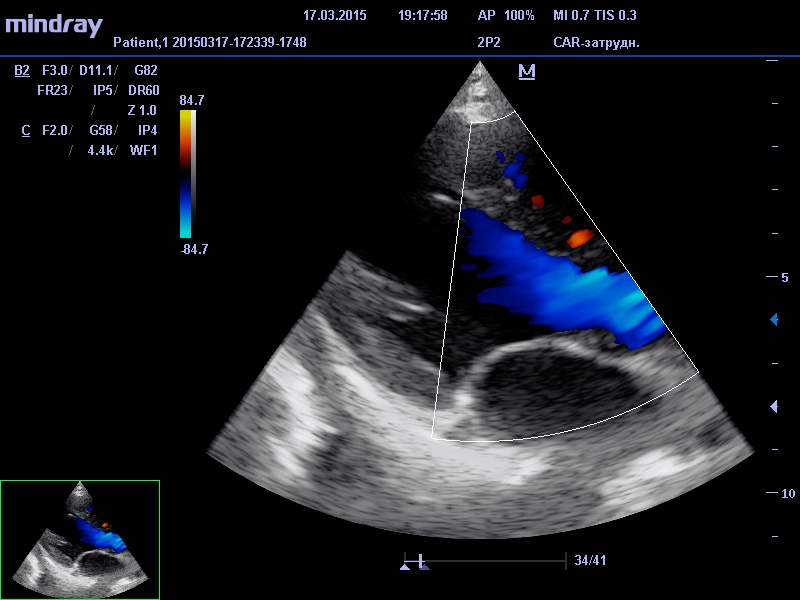

Благодаря УЗИ доктор может исследовать размеры сердца, стенок желудочков, оценить сердцебиение, проверить выяснить состояние сосудов, исключить или обнаружить тромбы или рубцы – то есть, сделать заключение о функционировании сердечно-сосудистой системы.

Смысл данной диагностической процедуры сводится к тому, что датчик посылает ультразвуковой сигнал (звуковая волна, которая не слышна человеческим ухом из-за своей невероятно высокой частоты) в область сердца. Из-за различной плотности тканей и расстояния ультразвуковые волны с различной скоростью отражаются от стенок сердца. Принимая обратный сигнал диагностический аппарат выстраивает картинку исследуемого органа.

Основными показателями, на которые обращают внимание специалисты-кардиологи при постановке диагноза больному, являются параметры правого и левого желудочка сердца, а также толщине перегородки между ними. Наиболее важные характеристики, это - масса сердечной мышцы, объем в состоянии покоя и объем в момент сокращения миокарда, количество выбрасываемой в результате сокращения крови. Эти данные специалист сравнивает с нормативами здорового человека, из чего делает выводы о состоянии здоровья кардиосистемы наблюдаемого пациента.